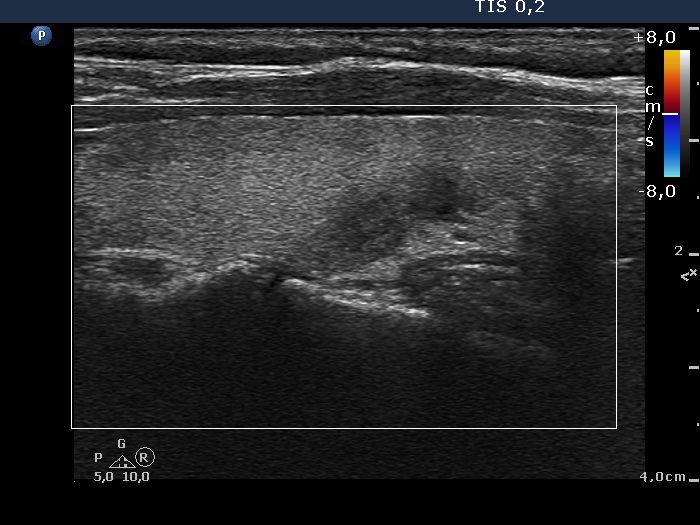

Follow-up investigation 2 months after the first visit (ultrasonographic picture 6)

Right lobe, longitudinal scan